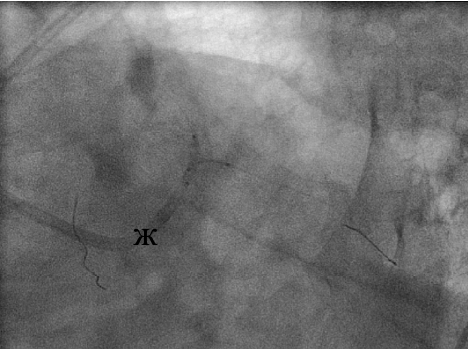

В связи с наличием выраженного стеноза устья ОВ (е) выполнена предилатация по методике «целующихся» баллонов (ж), после чего в ствол ЛКА с переходом на проксимальный сегмент ПМЖВ был имплантирован стент Cypher (з).